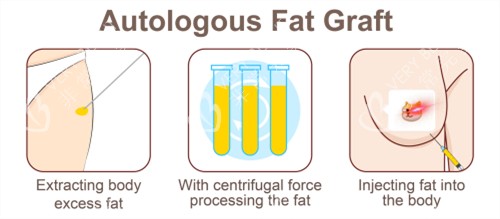

抽脂完成后,医生对抽取的脂肪进行了处理,将健康、有活力的脂肪筛选出来,准备注入乳房。接下来就是脂肪注射环节,医生小心翼翼地将处理好的脂肪一点一点注入乳房,调整乳房的形状和大小。手术持续了几个小时,结束后我被送回病房休息。

然而,当肿胀完全消失后,我却发现乳房只大了1个杯,这和我预期的结果相差甚远。我赶紧联系了医生,医生解释说,自体脂肪隆胸存在一定的脂肪吸收率。虽然抽取了3000cc脂肪,但并不是所有的脂肪都能在乳房内存活并起到增大的作用。

一般来说,脂肪的吸收率在30% - 70%左右,这受到多种因素的影响,比如个人体质、脂肪质量、手术操作等。我的体质可能对脂肪的吸收比较快,再加上手术过程中部分脂肪可能没有得到良好的血供,导致存活的脂肪数量有限,所以胸部增大的结果就不那么明显。